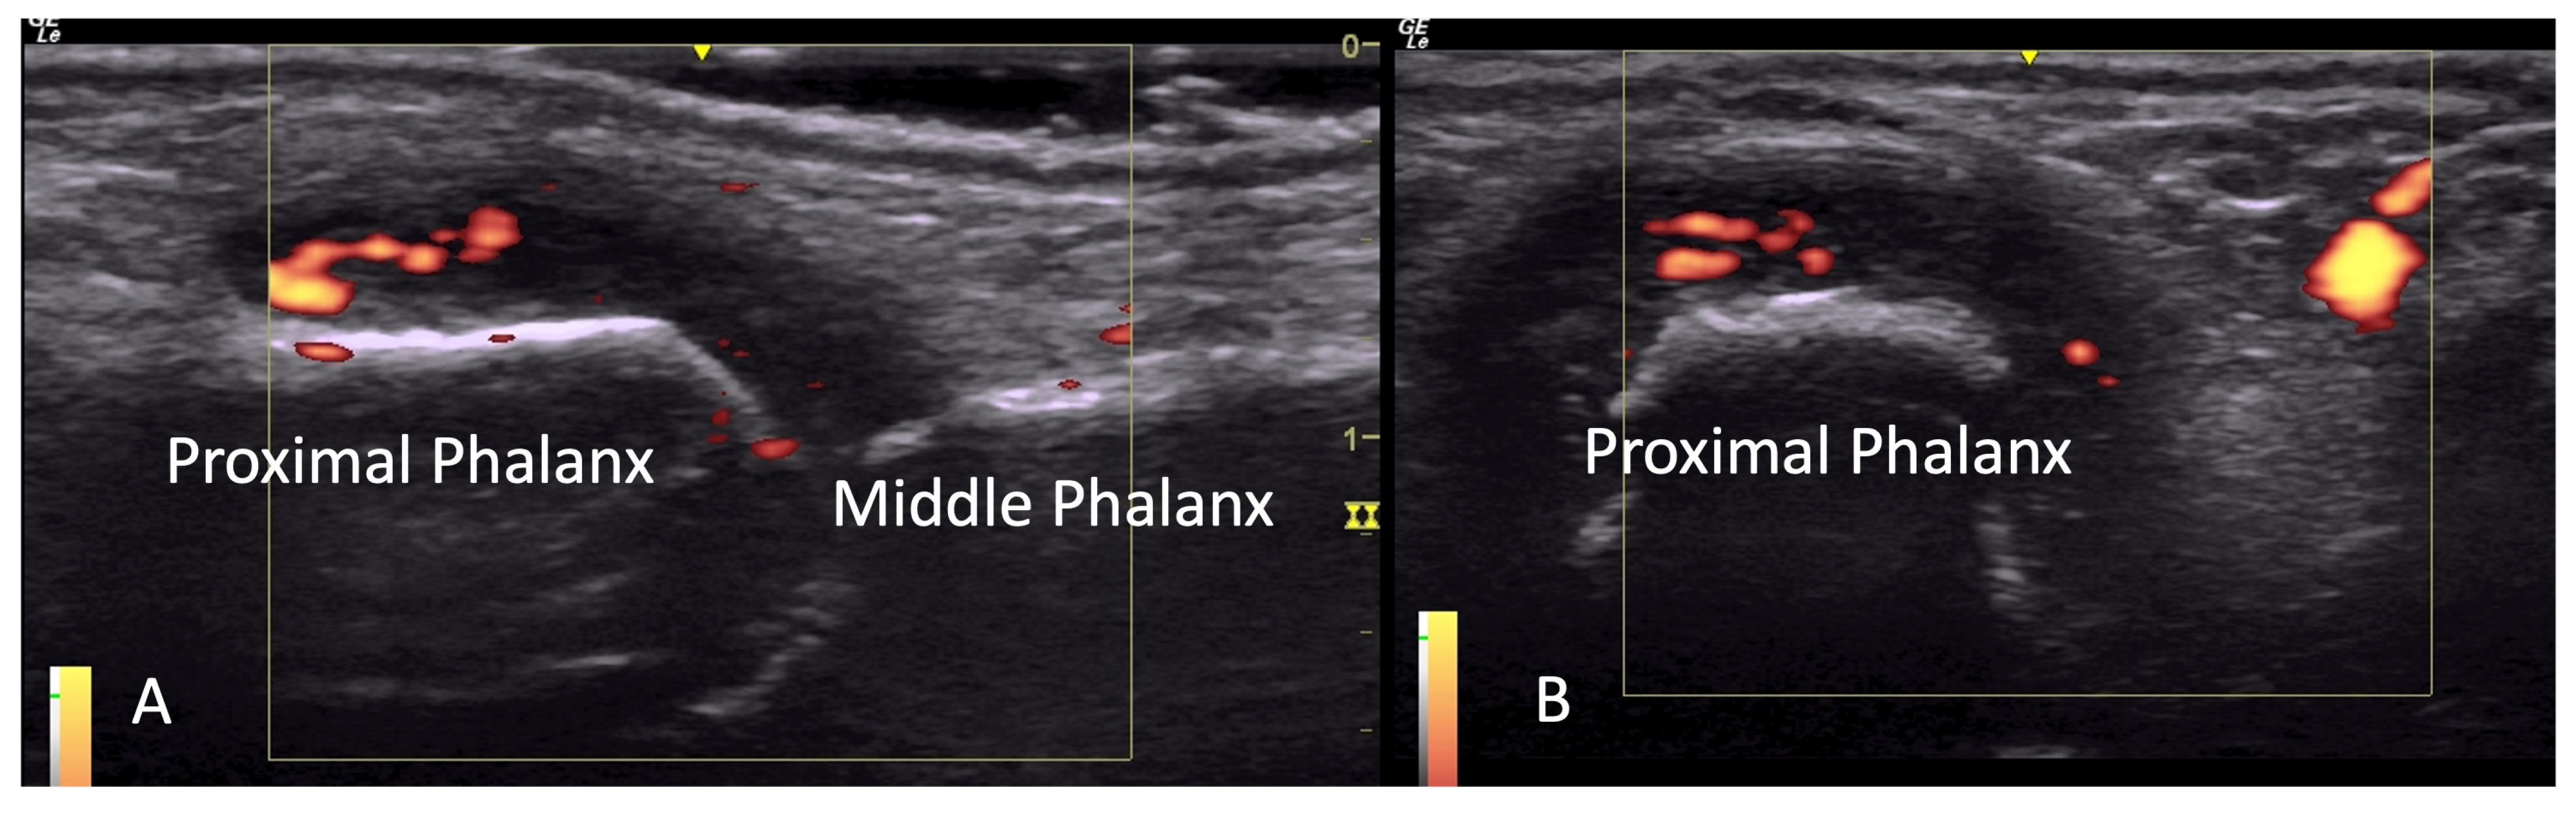

2.1.3. Acro-Osteolysis

4.1. Evaluation of the Fingers

4.1.1. Dorsal Aspect